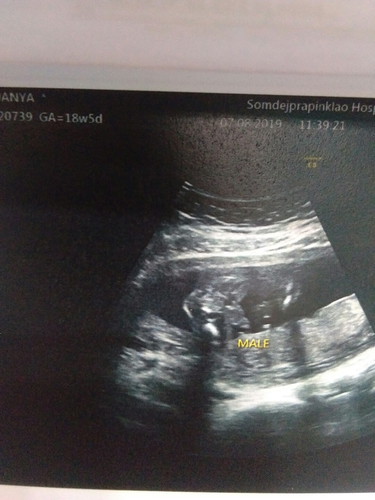

เห็นแล้วแอบกลัวเหมือนกันเลยค่ะ พ่อเค้าหวังมากว่าจะได้ลูกชายพอหมอบอกว่าผุชายเค้าดีใจมาก ช่วยดูใบซาวด์หน่อยค่ะ ว่าชายจริงๆใช่มั้ย55555 เริ่มกังวลแล้วค่ะแม่ๆ

ช่วยดูหน่อยคะ แต่หมอบอกผู้ชาย แม่ดีใจเพราะหวัง ผู้ชาย คนโตเป็นผู้หญิงคะ แต่พอมาบ้านคนแถวบ้านบอกระวังนะซาวผิด อีแม่แอบใจเสีย แต่ ไม่หญิง หรือ ชาย ก็รักหมดคะ

หวังชายเหมือนกันคะ 2ท้องแรกหญิงแล้ว หมอบอกตอนแรกว่าชาย แต่ถ้าให้ชัวร์จะซาวน์ซ้ำ พอครั้งที่2ตามในรูปเลยคะ หมอก็บอกชายเหมือนเดิมคะ